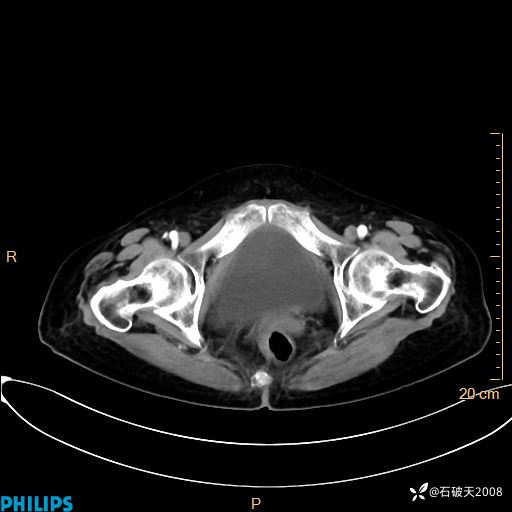

MIP